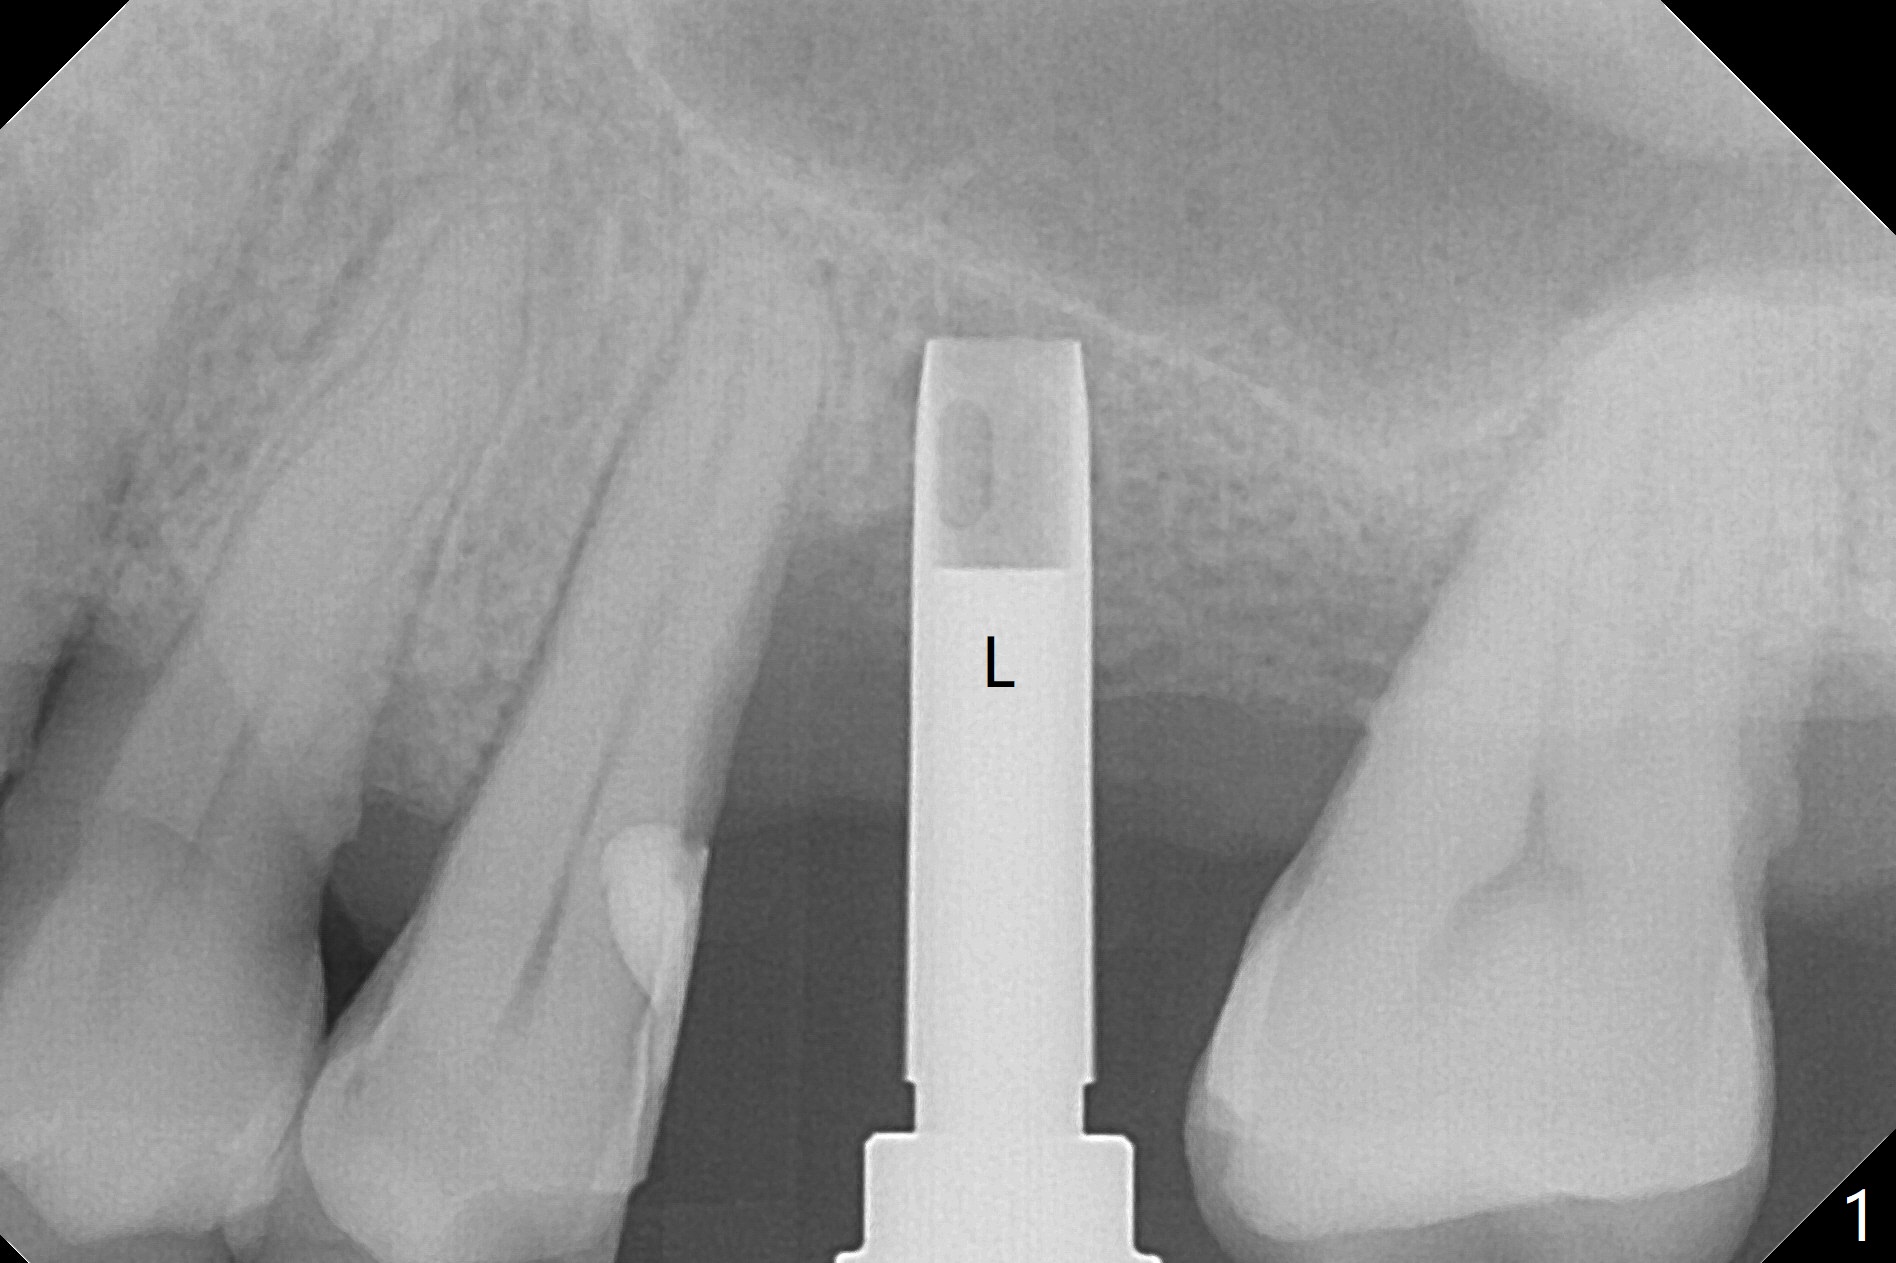

Trajectory of sinus lift without guide at #14 is off (Fig.1 (Magic Sinus Lifter (L) for 9 mm (gingival level)) and needs to be corrected (Fig.2 long line) by re-using 4.8 mm Magic Drill. Following placement of PRF membrane and Demineralized Cortical Allograft (.125-.850 mm) for sinus lift (Fig.3 black dashed line), a 4x10 mm dummy implant is placed with off trajectory. The latter will be fixed by using Lindmann bur to remove the bone distal (Fig.4). The result is less satisfactory with placement of 4.5x10 mm dummy implant (Fig.5). It appears necessary to initiate a new osteotomy (Fig.6 long black line). In fact the result is appealing (Fig.7). The final implant (5x7.3 mm) seems to be placed ideally shown by PA (Fig.8) and BW (Fig.9). Immediately postop CT demonstrates distal defect (Fig.10 *;3-D) and supracrestal placement palatal (Fig.11 P; coronal section). More allograft is then placed in these 2 areas. In all, it is difficult to establish a correct osteotomy without guide. The patient return for uncover 3.5 months postop, although there is a small hole in the middle of the incision (Fig.12). The crown/abutment becomes loose less than 1 month post cementation when the patient chews something tough. It is more related to the unfavorable implant/crown ratio. It is loose again 2 months later. Screw driver is buried inside the abutment with plumber tape. When it is loose for the 3rd time 13 months post cementation, the existing screw driver with a created slot (for retention) is buried without plumber tape after retorque at 35 Ncm (Fig.13). A tissue-level implant should have been used.